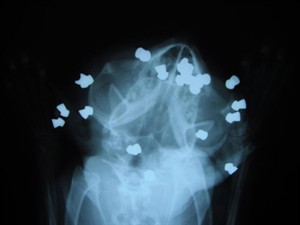

Sarnia and District Humane Society manager Donna Pyette says a male cat was brought to them on Sunday with 17 pellet gun shots in his head.

She said they are hoping he will be strong enough by early next week to undergo surgery to remove some or all of the pellets lodged in his head.

However, she says Joe will lose one of his eyes due to irreparable damage from his injuries.

The humane society believes someone held the cat or immobilized him somehow before he was shot with the pellet gun, Pyette said.